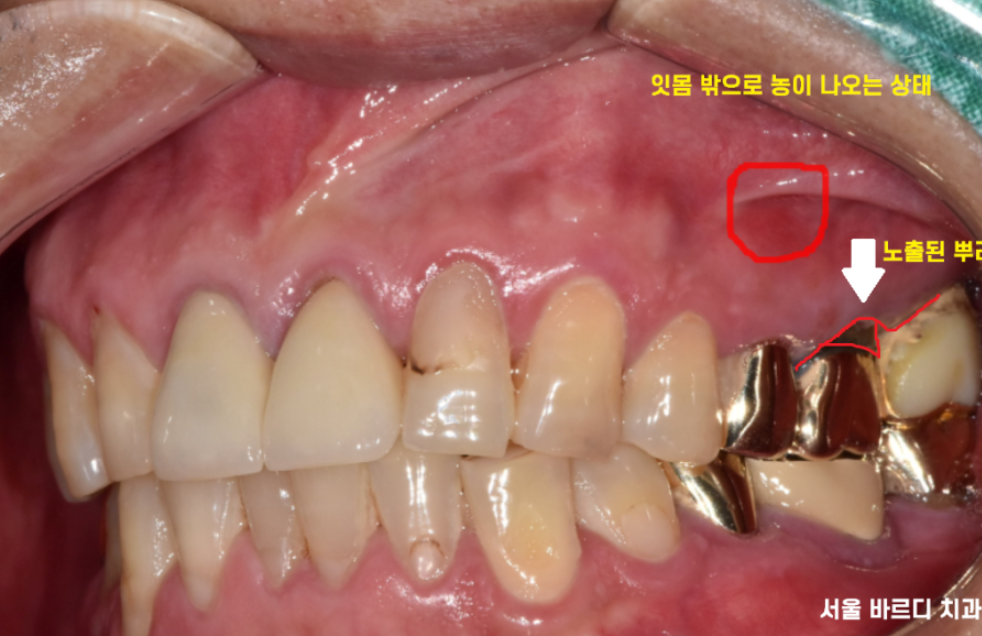

구강 내 사진입니다.

눈으로 보이는 부분에서도

좋지 않은 것은 마찬가지..

전반적으로 잇몸이 조금씩 내려간 부분은 있었지만

제일 문제가 되는 부분은 왼쪽 위였습니다.